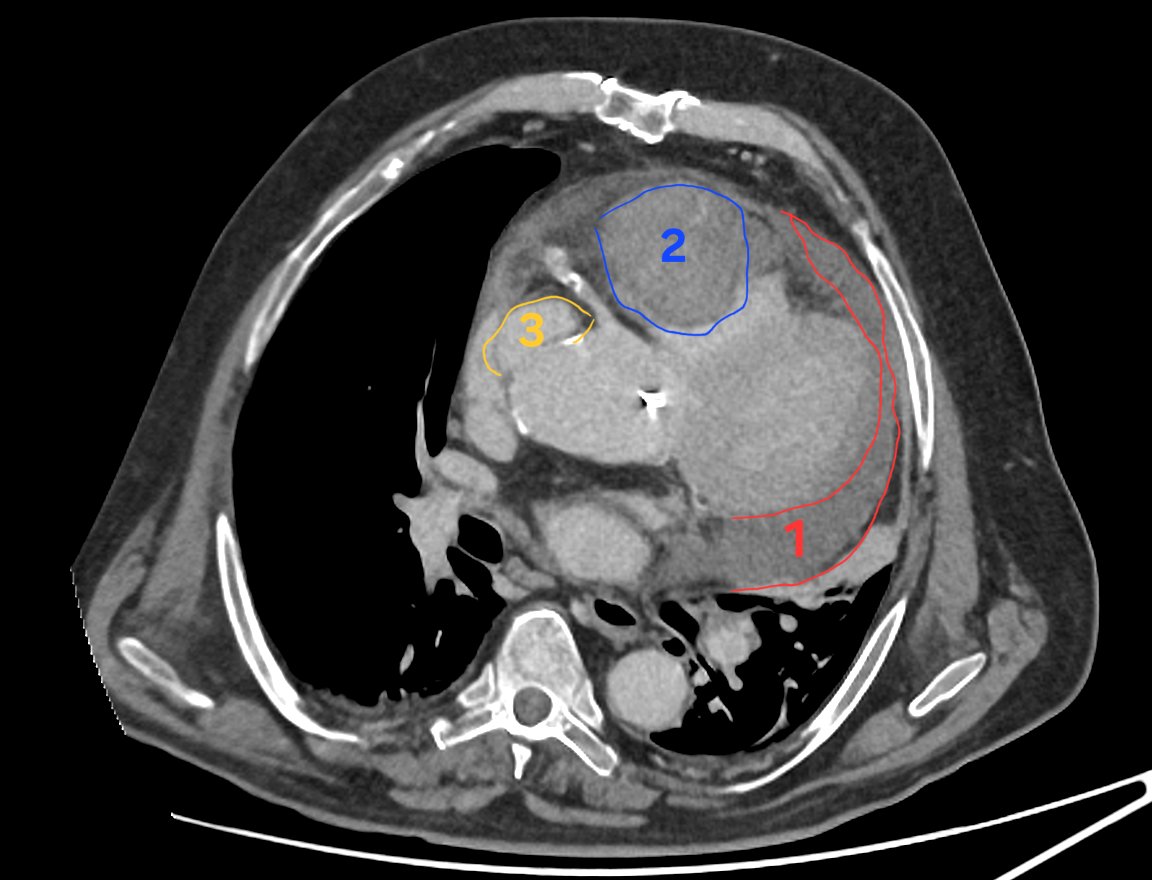

En 1 sur l'image : épanchement péricardique circonférentiel, assez dense. C'est l'hémopericarde. En règle général tout le monde le voit, c'est la première anomalie à attirer l'oeil. La voir doit faire demander : pourquoi ??

En 2 : un hématome intra péricardique. Ça c'est plus dur à détecter et déterminer, regardez la vidéo pour bien comprendre. Ça nous fait affirmer que 1 est forcément pathologique, et doit nous faire absolument rechercher la cause.

En 3 : une image d'addition en regard de l'aorte ascendante. Ça n'est PAS normal. C'est très dur à détecter quand on n'a pas l'habitude ou qu'on ne le recherche pas... C'est ça la cause de l'hémopericarde. Regardez la vidéo pour bien voir comment on repère cette anomalie

Bonus : la cause est visible ici ! En limite de champ on voit un bout de bioprothèse aortique. Le patient avait déjà été opéré... Il y a probablement eu endocardite (d'où la fièvre...) et rupture aortique sur ancien trajet de CEC...

Alors que l'on pensait à une embolie ou une infection chez cet homme avec fièvre et douleurs thoraciques... Le scanner découvre une rupture aortique avec hémopéricarde 😱 Revenons en détails sur les 3 choses essentielles à ne pas rater sur cette coupe, avec petit bonus après ⬇️

Il y a 3 choses essentielles à voir sur cette seule coupe axiale, injectée, acquise au temps portal. Evidemment les 3 sont reliées et permettent de faire le diagnostic global ! Un indice : ce n'était pas ce qui était suspecté par les urgentistes 😅

🤯Un cas très difficile, mais tout est sur cette unique image de scanner : arriverez vous à faire le diagnostic ? Contexte donné par les urgentistes : 72 ans, pneumopathie, mauvaise évolution clinique à J3 du traitement. Recherche EP, surinfection, abcédation. 🤔Vos avis ?